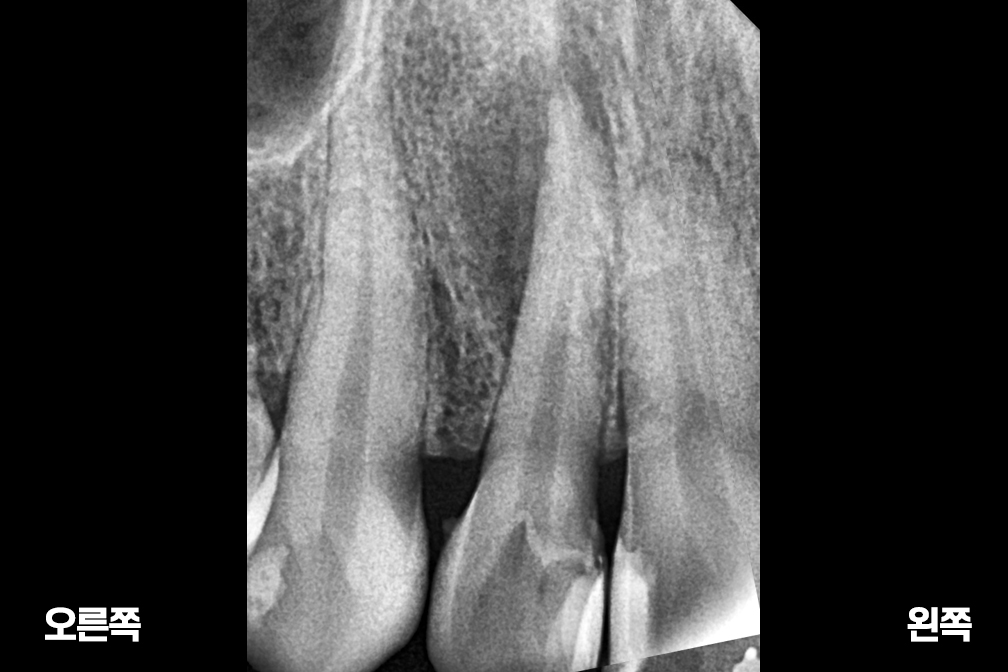

Before 2025년 9월 8일